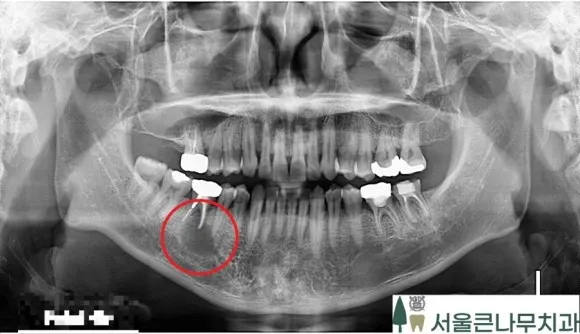

쉽게 말하면 낭종은 염증 주머니라고 생각하면 됩니다. 옆 파노라마 사진을 보면 바로 확인할 수 있습니다.

다른 부위에는 보이지 않지만 빨갛게 동그라미 친 부분 쪽에는 치아 밑으로 검은 부위 보이시죠? 이것을 낭종이라고 칭합니다.

위 CBCT 사진을 보시면 더 명확히 확인할 수 있는데요. 주위 치아와는 다르게 뿌리 아래로 동그란 검은 주머니가 보이시나요? 엑스레이에서 검은 부위는 염증이라고 생각하면 됩니다. 당일 뼈이식 동반 임플란트 수술을 진행해야 합니다.